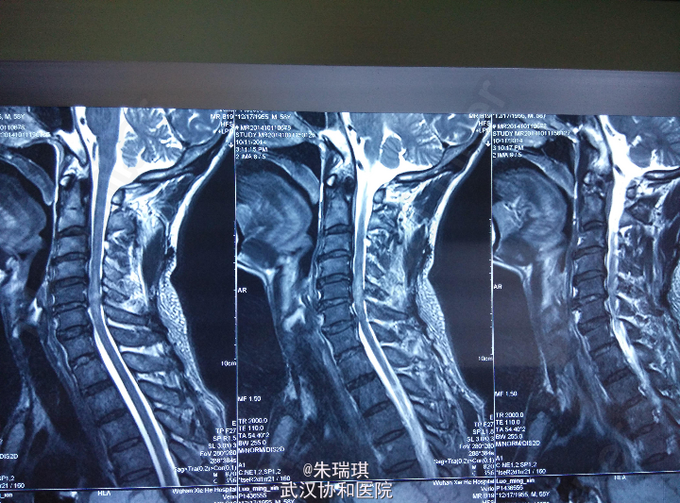

男,58岁 主诉:外伤致颈部疼痛、活动受限、四肢无力3天 现病史:患者于2014-10-8下午4点左右骑摩托车摔伤,有短暂昏迷史(无顺行性或逆行性健忘史)。无恶心呕吐、胸闷心慌、头痛头晕等症状。曾在当地医院诊治(具体诊疗过程不详),门诊以“颈部外伤伴截瘫收入院” 患者起病来,精神、食欲一般,小便行导尿术,大便未解,体力体重无明显变化。

查体:T:36.8℃,P:72次/分,R:20次/分。神志清楚。心肺腹未见明显异常。 颈椎生理曲度变浅,C4-6棘突压痛、叩击痛。右手握力2级,左手握力2级,双上肢三角肌、肱二头肌、肱三头肌肌力3-级,双侧股四头肌、股二头肌肌力3+级,四肢及胸腹部皮肤感觉无明显异常,腹壁浅反射减弱,肛周反射消失,双膝反射减弱。 实验室检查:中性粒细胞81%,血红蛋白、白细胞正常,凝血功能正常,AST49U/L

初步诊断:1、颈椎脊髓损伤伴不全瘫; 2、颈椎棘突骨折 治疗:改善神经,营养循环,后期康复治疗。

颈椎脊髓损伤很容易导致高位截瘫,本例脊髓损伤不完全,经过康复锻炼已恢复大半,脊柱损伤病人的转运一定注意不要损伤脊髓,否则后果严重。